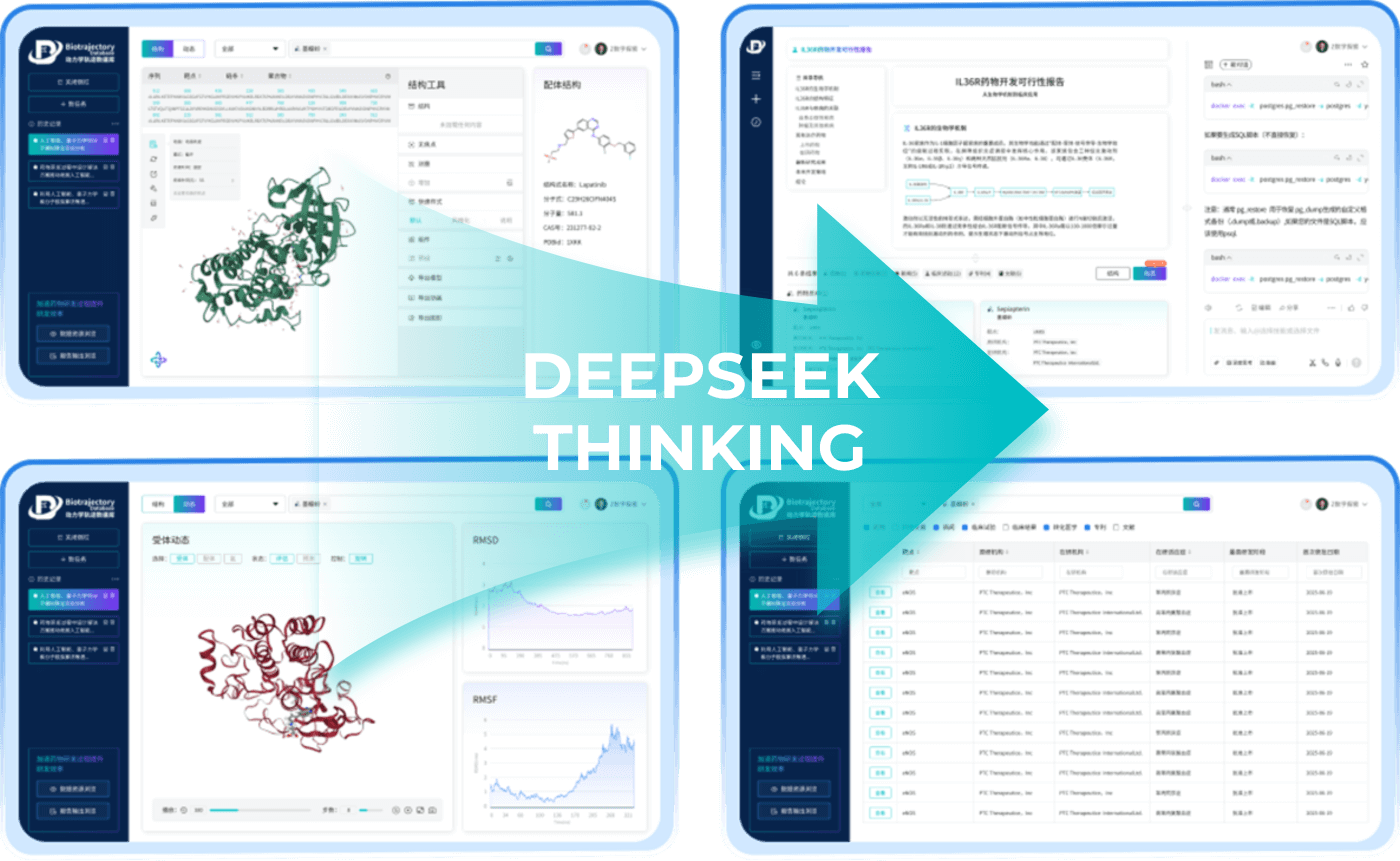

Biotrajectory AI meticulously analyzes vast amounts of literature, patents, and clinical data,

providing the clarity and speed you need to make

breakthrough decisions.

By supporting every stage of early discovery,

Biotrajectory AI transforms unstructured

scientific knowledge into

structured, actionable intelligence across the following analytical

modules:

Literature & Patent Analysis

We provide a comprehensive review of

research backgrounds, biological functions, and the

entire R&D history of

related drugs. Our system also collates

and interprets

compound patents,

offering insights for Best-in-Class (BIC)

or First-in-Class (FIC)

development

strategies.

Structure &

Molecular Design

We model target-drug binding,

analyze structure-activity relationships,

and propose new molecular designs.

Our AI evaluates and screens potential

molecules to maximize your chances of

success

in lab validation.

Clinical Analysis

We analyze the success and failure of drugs in clinical trials to help you refine

your development strategy.